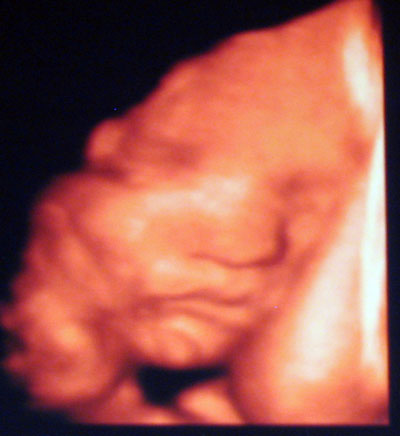

Szép nagyok vagytok már